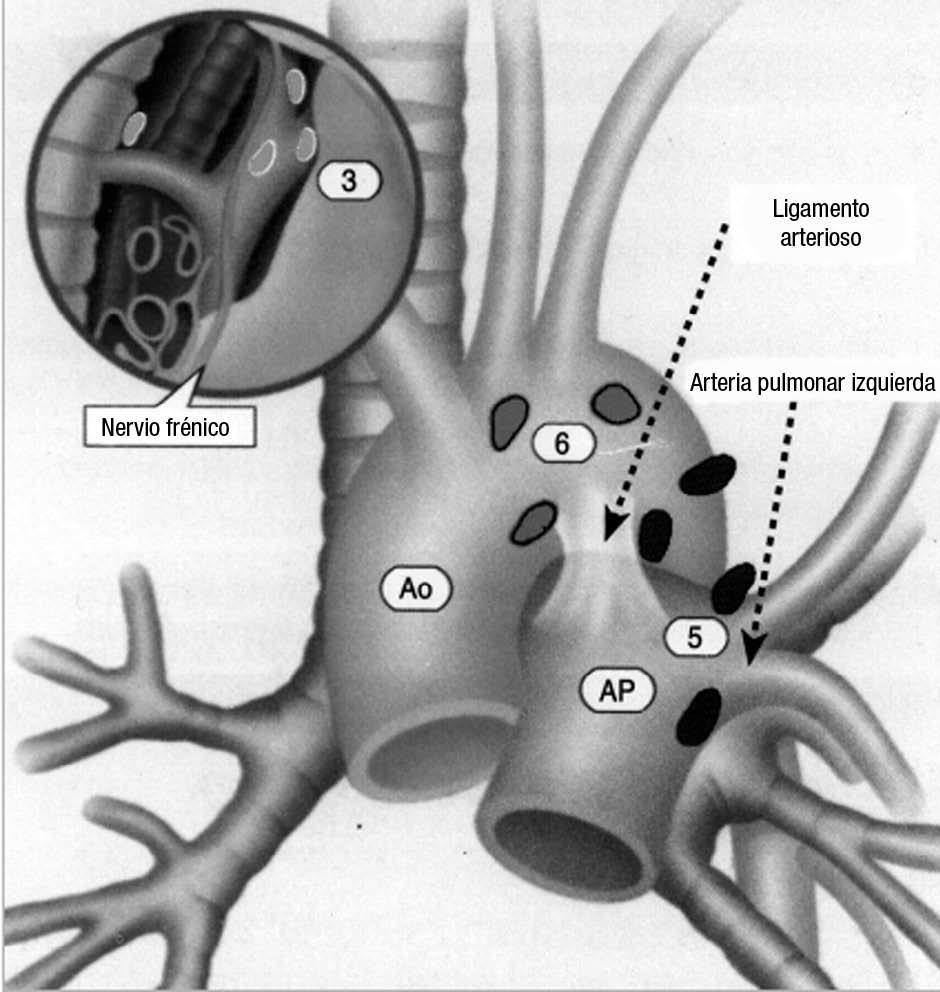

La precisión de la TC para predecir la afectación ganglionar mediastínica, pese a la ayuda que suponen las reconstrucciones MPR y 3D en la valoración de determinados territorios ganglionares (espacio subcarinal, hilio o ventana aortopulmonar) (fig. 11), sigue teniendo muchas limitaciones. El único criterio que se emplea para considerar que un ganglio es patológico es el tamaño (cuando el eje corto es mayor de 10 mm, salvo en el espacio subcarinal que se acepta hasta 12 mm). El empleo únicamente de criterios de tamaño hace que la TC sea una técnica poco precisa en la valoración de la afectación ganglionar. En un metaanálisis reciente13 la sensibilidad global de la TC para estadificar el mediastino fue de un 57%, con una especificidad del 82%, un valor predictivo positivo (VPP) del 56% y un valor predictivo negativo (VPN) del 83%. Lo que es innegable es la capacidad de la TC para mostrar un mapa de los ganglios tanto hiliares como mediastínicos (fig. 12), lo cual es de gran utilidad en la determinación del factor N. La valoración del territorio hiliar puede ser compleja por la agrupación de estructuras vasculares, por lo que además de la opacificación adecuada de éstas, es de utilidad la identificación de la pérdida del ángulo de la bifurcación (carina secundaria), ya que el eje corto significativo en este territorio es de 3 mm. Como ya hemos comentado, también es de gran ayuda en esta localización el empleo de reconstrucciones (fig. 11)5.

Fig. 12.--Estaciones ganglionares para la estadificación del cáncer de pulmón. Las reconstrucciones multiplanares (MPR) son de gran ayuda para precisar los territorios ganglionares afectos. Correlación de los territorios ganglionares entre el mapa ganglionar de Mountain y Dressler y una reconstrucción coronal de un paciente con afectación adenopática mediastínica e hiliar bilateral. (A y B) Ganglios mediastínicos superiores e inferiores e hiliares. (C y D) Ganglios aórticos. AP: arteria pulmonar. Ao: aorta.

La ecografía endoscópica y punción aspiración con aguja fina (EE-PAAF) se está introduciendo como una técnica prometedora en la valoración del mediastino. Puede visualizar directamente los territorios 4L, 5, y ganglios seleccionados del 6, 7 y 8. Los paratraqueales derechos a menudo no se ven por la interposición del aire de la tráquea. Si sólo se aplican criterios morfológicos, la sensibilidad y la especificidad de la EE-PAAF son respectivamente del 78 y 71%, sin embargo si se realiza la PAAF las cifras de sensibilidad son de un 88%, la especificidad del 100% y la exactitud diagnóstica del 82%16. El rendimiento de la prueba aumenta con el número de ganglios muestreados y con la realización de al menos 3 pases.